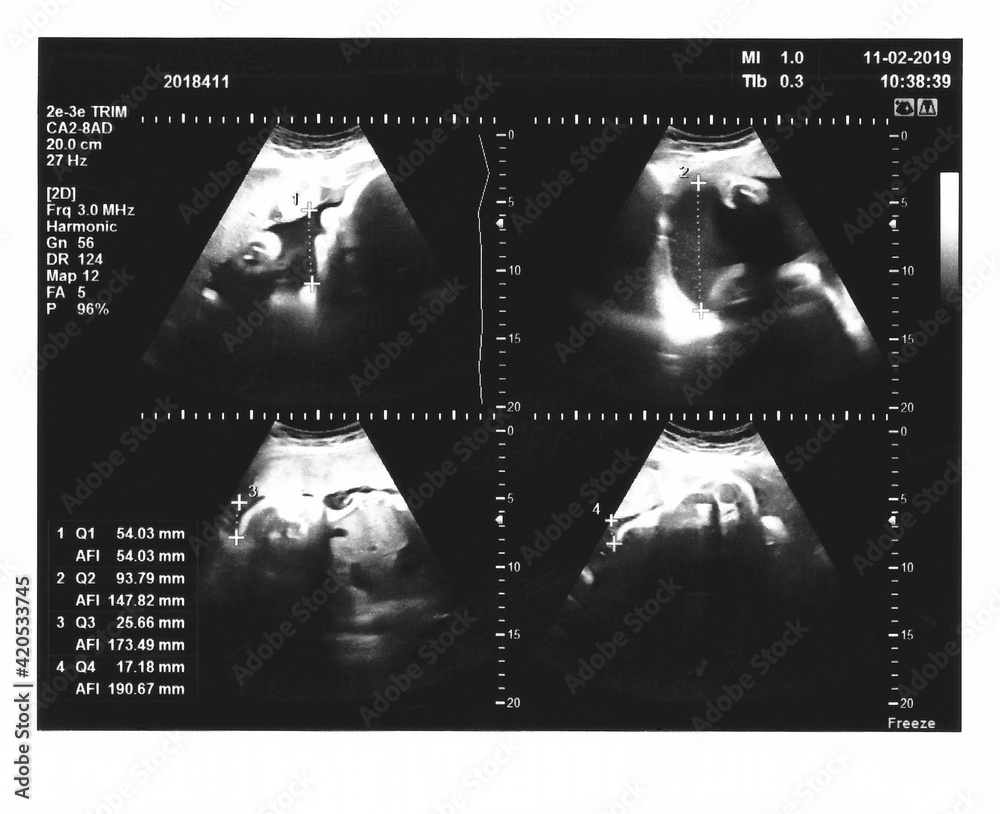

From stock.adobe.com

Sonogram measuring amniotic fluid Stock Photo Adobe Stock How Do You Measure Amniotic Fluid two main methods are used to communicate amniotic fluid levels: Amniotic fluid that’s tinted brown or green means. the fluid volume infused at each amnioinfusion ranges from 300 to 800 ml of warmed isotonic fluid, following general guidelines of. qualitative or semiquantitative assessment of amniotic fluid volume (afv) is a standard component of every. amniotic fluid. How Do You Measure Amniotic Fluid.